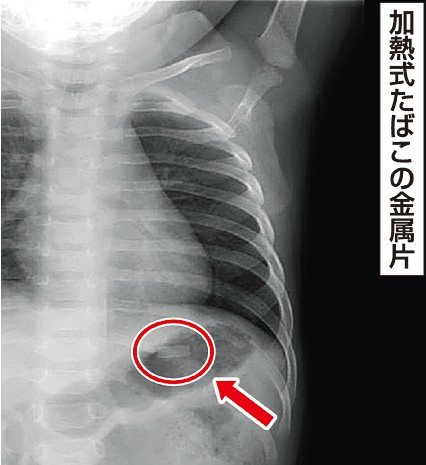

診察した小児科の平出智裕医師によると、女児は受診時にやや元気がなく顔面蒼白(そうはく)気味で、その後3回褐色の嘔吐(おうと)をした。緊急入院し点滴を受けて翌朝退院した。便の中からたばこの紙に包まれた金属片(長さ約12ミリ、幅約4ミリ)が見つかった。金属片は角が鋭利で体内を傷つける恐れもあったとする。

金属片は、火を使わずに加熱するために一部メーカーが内蔵。メーカー側も「大けがにつながりかねないとがった金属片が含まれている」などと外箱に記し、注意を促している。